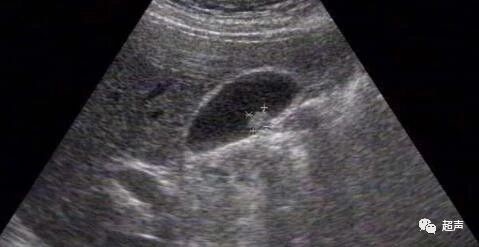

我们通常经B超检查发现的胆囊息肉,全称应为胆囊息肉样病变,是形态学和影像学诊断的概念,是指来源于胆囊壁并向胆囊腔内突出或隆起的病变。

从病理学的角度主要包括胆囊息肉和胆囊腺瘤两种,前者是非肿瘤性息肉,如胆固醇息肉,炎性息肉等;后者为肿瘤性息肉,可恶变,是胆囊癌的癌前病变。

胆囊胆固醇息肉最多见,占胆囊息肉样病变的95%以上,多为多发,实际上是胆汁中胆固醇过饱和而析出的胆固醇结晶,不会恶变,除胆囊颈部息肉外多无明显症状,通常无需手术治疗,尽量避免进食高胆固醇类食品如:鸡蛋(尤其是蛋黄)、肥肉、海鲜、无鳞鱼类、动物内脏等即可,药物治疗主要以调节胆固醇代谢和调节胆汁中的成分为主,效果均不甚理想。